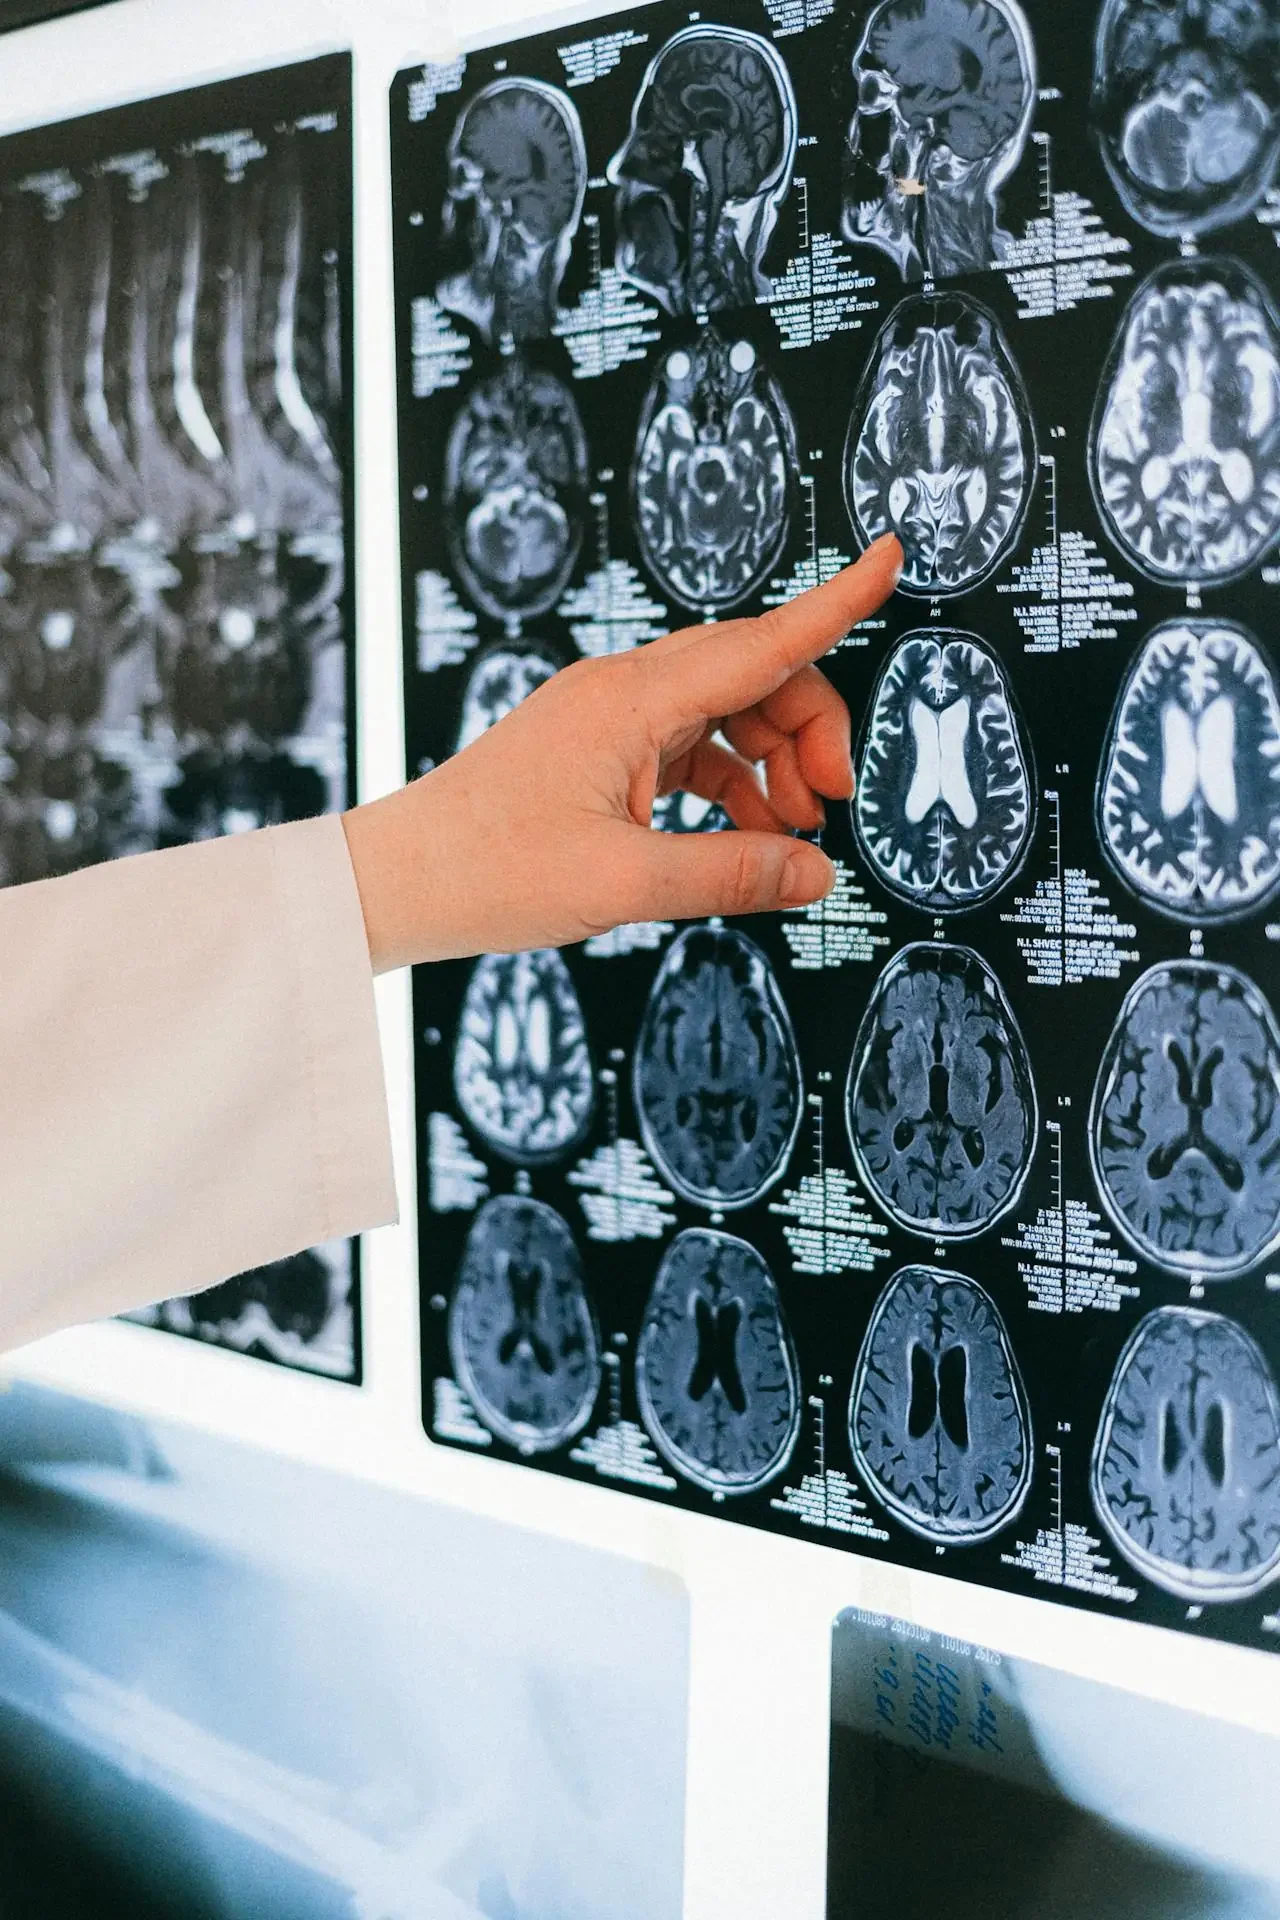

Su recuperación se logró gracias a un ensayo clínico experimental en el Instituto Gustave Roussy de París, donde participó en el estudio BIOMEDE. Fue uno de los seleccionados para recibir el medicamento everolimo, una terapia utilizada en otros tipos de cáncer, aunque sin eficacia demostrada para el DIPG. Contra todo pronóstico, las resonancias mostraron la desaparición completa del tumor.

El doctor Jacques Grill, responsable del programa de tumores cerebrales del instituto, afirmó que nunca se había registrado un caso similar. Según los investigadores, una mutación genética rara en el tumor de Lucas podría haberlo hecho más sensible al tratamiento. Aunque otros siete pacientes mostraron mejoría clínica, ninguno logró una remisión total como la de Lucas.